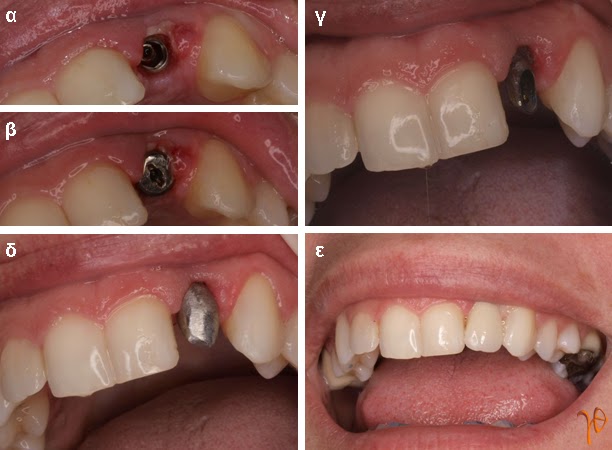

Οι πιο συχνές βλάβες από ερεθισμό στο στόμα είναι τα αντιδραστικά ινώματα (Εικόνες 4 και 5).

Εικόνα 4. α. Ίνωμα της υπερώας από χρόνιο ερεθισμό ολικής οδοντοστοιχίας (βέλος), β. Μετά την χειρουργική του αφαίρεση.

Εικόνα 5. α. Ίνωμα της παρειάς από χρόνιο ερεθισμό της σύγκλεισης στην περιοχή (βέλος), β.Μετά την χειρουργική του αφαίρεση.